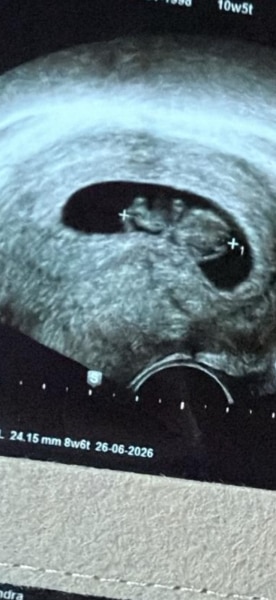

Hallo ihr Lieben,   ich bin heute bei 8+6 und unser ET ist jetzt offiziell der 26.06.2026. Morgen bin ich also 9+0 (10 SSW) Irgendwie ein kleiner Meilenstein für mich und ich bin etwas beruhigter jetzt, da das Risiko ja gut gesunken ist. Wie groß waren eure zu der Zeit?

Bild zu Größe Baby - Forum für Juni - Mamis

Hallo Glückwunsch zur Schwangerschaft und ein süßes Bildchen hast du bekommen. Von der Woche hab ich nix. Ich hatte bei 10+1 Termin, da waren sie 3,1 cm & 3,3 cm groß.  LG